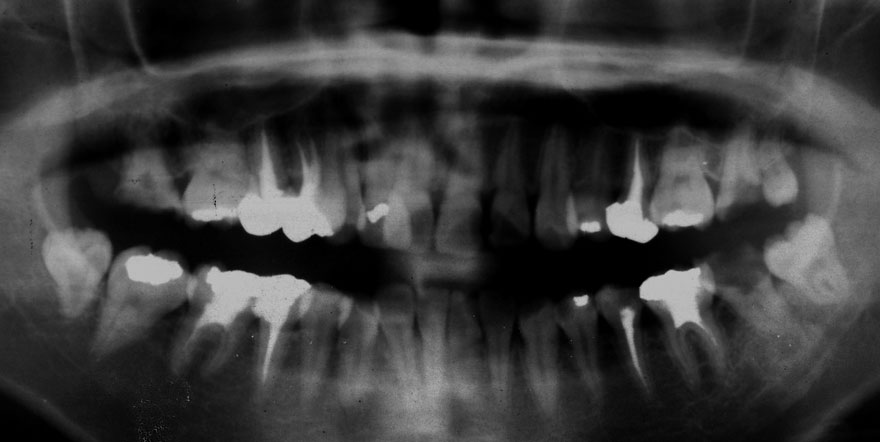

初診時 19歳 女性

虫歯多発傾向

31年後 50歳